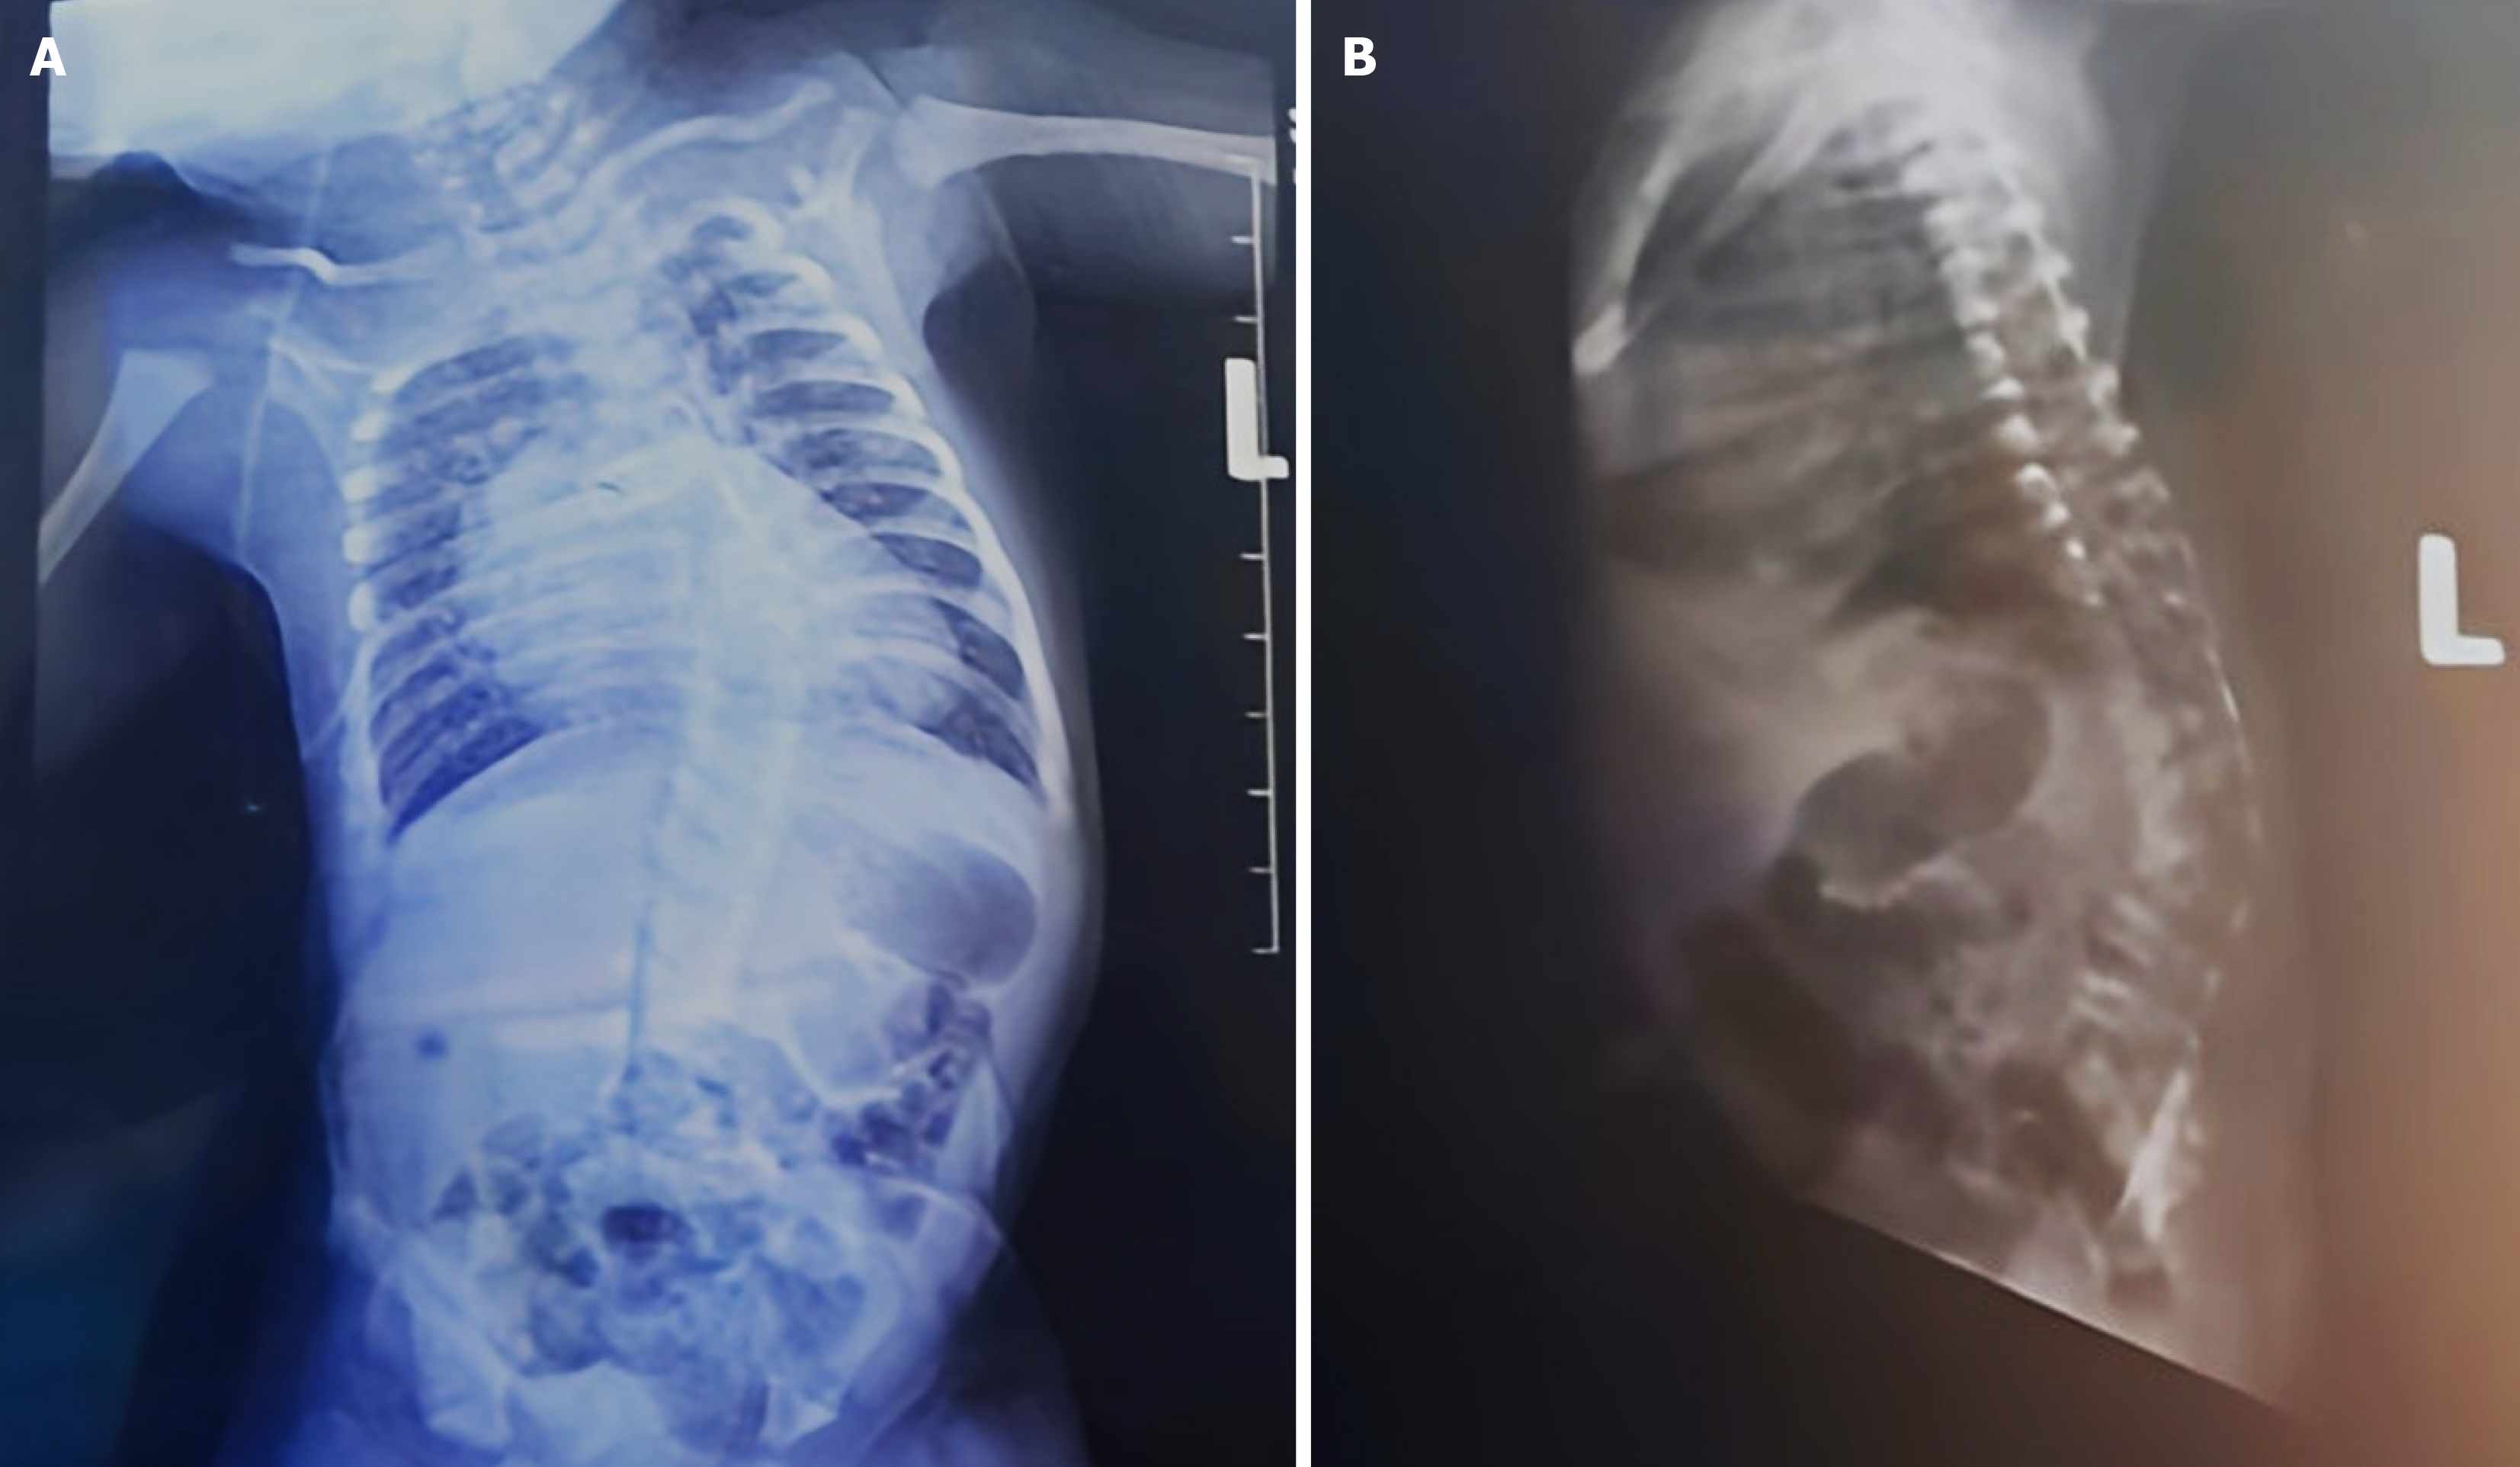

Figure 2 The neonate's X-ray image.

A: The spine's altered curvature in anterior-posterior view; B: The spine's altered curvature in lateral view.